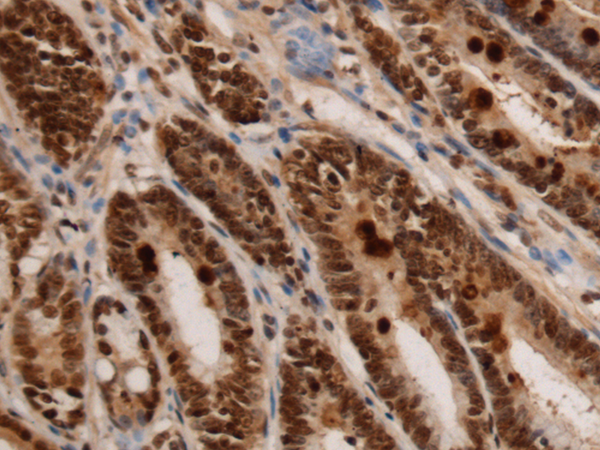

IHC positive control: |

Human colorectal cancer and Human gastric cancer |

IHC Recommend dilution: |

150-300 |